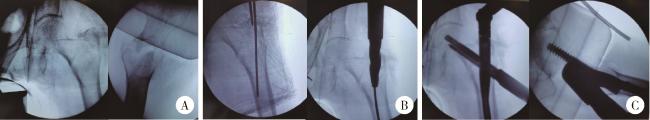

图2 患者股骨粗隆间骨折闭合复位内固定术术中透视X线片

Figure 2 X-ray in closed reduction and internal fixation of femur intertrochanteric fracture of paitient

A, following closed reduction, the X-ray of the left hip confirmed a well-reduced fracture; B, after inserting the guide pin into the femoral medullary cavity, reaming was performed; C, subsequently, the proximal femoral intramedullary nail and lag screw were inserted, and an X-ray of the femur was taken.